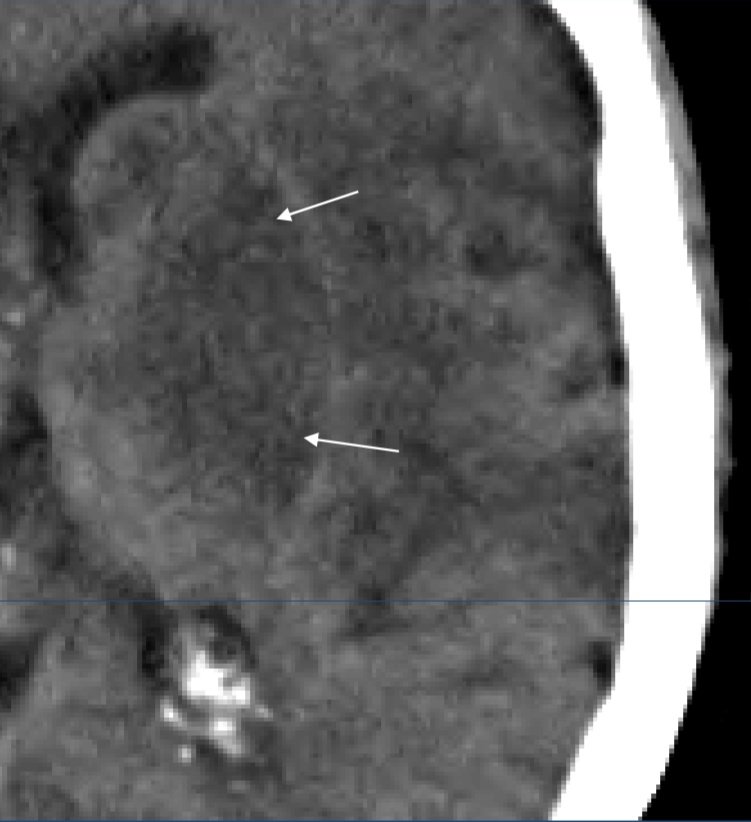

Se Observa El Signo De La Cuerda Dado Por La Hiperdensidad De La Download Scientific Diagram

Multimedia En Medicina 34 Signo De La Cuerda Interconsulta On Line